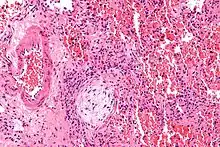

![]() | |

| Micrograph showing a Masson body (off center left/bottom of the image – pale circular and paucicellular), as may be seen in cryptogenic organizing pneumonia. The Masson body plugs the airway. The artery associated with the obliterated airway is also seen (far left of the image). H&E stain. | |

Histologically, cryptogenic organizing pneumonia is characterized by the presence of polypoid plugs of loose organizing connective tissue (Masson bodies) within alveolar ducts, alveoli, and bronchioles.